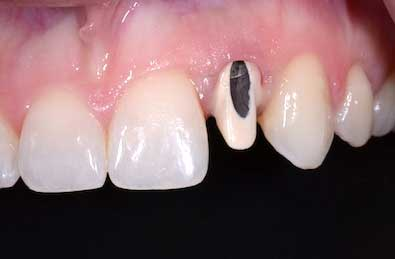

RELATED |Who should adjust mandibular incisal edges, and when?RELATED |Cementation of full-contour zirconia restorations When trying in an all-ceramic restoration on an implant abutment to confirm the esthetic outcome prior to its cementation, I suggest following these steps:1. If the screw access hole is on the labial aspect, it must be closed or blocked out, or the “black hole” will create a shadow and negatively impact the value of the all-ceramic restoration. This same shadow will occur if this is not managed correctly at the time of insertion.2. To close or block out the access opening, first place Teflon tape into the access opening. Over the tape, place an opaque temporary cement or opaque resin that totally masks the access hole. Ideally this should be the same process and materials that will be used at the time of try-in and final cementation of the restoration. If there is any metal exposed or shadow remaining, it will influence the esthetic appearance of the restoration.3. When doing the try-in, there are two reasons that I recommend using a try-in paste.A. First, it most closely simulates the color, value, and opacity of the final cement that will be used.B. Second, it connects the intaglio surface of the restoration to the prepared tooth or implant abutment. This “bridging of the gap" between the restoration and the abutment must occur to evaluate the esthetics of the restoration.

Fig. 2: If the access opening is left open, the alloy and the shadow will lower the value of the crown, making it appear too gray.